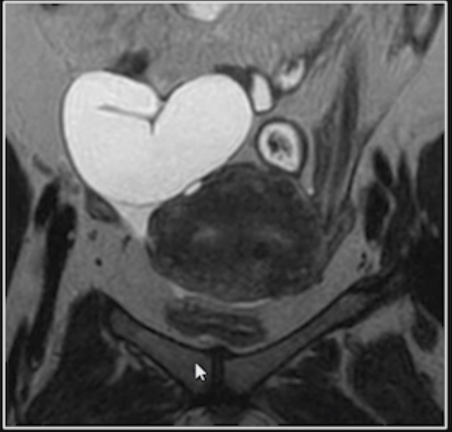

Hidrossalpinge